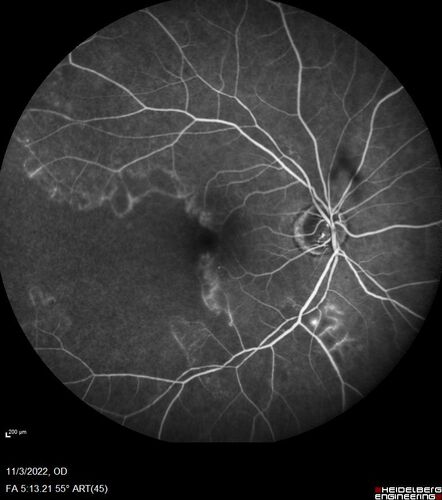

Coats Plus Syndrome - Cerebroretinal microangiopathy with calcifications and cysts (CRMCC)

38 year old female CTC1 positive with Coats Plus Syndrome. This case was published https://pmc.ncbi.nlm.nih.gov/articles/PMC10649444/